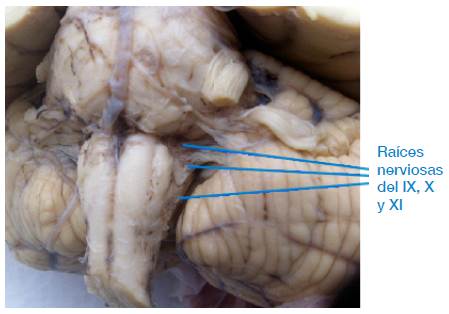

De los 67 troncos encefálicos estudiados, se encontró que en ninguno de ellos las raíces nerviosas de los nervios glosofaríngeo, vago y accesorio hacían su aparición como origen aparente en el surco retro-olivar, tal como se describe en la literatura consultada. Se observó que, en el 100% de las piezas neuroanatómicas estudiadas, el origen aparente de estos tres nervios craneales forma una línea continua de raicillas que se localiza entre 2mm a 3mm por detrás del surco retro-olivar, en sus lados derecho e izquierdo, concretamente en las áreas retro-olivares, tal como se puede apreciar en las Figuras 1, 2, 3 y 4. Además, no se evidencia ningún surco en aquel sitio por donde emergen las raicillas de estos nervios craneales.

Raíces nerviosas de los nervios craneales glosofaríngeo, vago y accesorio.

Figura 2: Raíces nerviosas de los nervios craneales glosofaríngeo, vago y accesorio.

Fuente: Elaboración propia.

Múltiples autores indican que el origen aparente de los nervios glosofaríngeo, vago y accesorio se encuentra en el surco retro-olivar 5,6,18,19 o surco post-olivar 7,9,20. Sin embargo, una inspección más detallada en las muestras estudiadas sobre dicho sitio de origen revela que tal descripción no es cierta y carece de precisión, por lo que se sugiere hacer más estudios en otros lugares geográficos y con una muestra mayor, esto con el fin de precisar dicho sitio de emergencia o revaluar este concepto. En los 67 troncos encefálicos utilizados para este trabajo, se encontró que en ninguno de ellos las raicillas nerviosas de estos nervios craneales emergen por los surcos retro-olivares. En el 100% de las piezas neuroanatómicas analizadas, se evidenció y registró fotográficamente que las raicillas nerviosas hacen su aparición entre 2mm a 3mm por detrás del surco retro-olivar en sus lados derecho e izquierdo, concretamente en las áreas retro-olivares; además, contrario a lo que se registra en la literatura, no se observó la presencia de ningún surco en aquel sitio por donde emergen las raicillas nerviosas.

Los nervios craneales glosofaríngeo, vago y accesorio no tienen su origen aparente en el surco retro-olivar, como tradicionalmente se describe en los textos y artículos referenciados. El verdadero origen aparente de estos nervios ocurre entre 2mm a 3mm por detrás del surco retro-olivar, lugar donde se aprecia una línea continua de raicillas nerviosas que se hacen visibles en ambos lados de la médula oblongada, en específico en las áreas retro-olivares. Tampoco se encontró evidencia de ningún surco en el sitio donde supuestamente emergen las raicillas de estos nervios craneales, distinto a lo que se describe en la literatura.